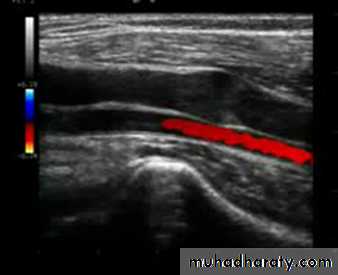

• Duplex Examination

DVT

Size of veins

Map out superficial veins

Locate the site of reflux

Find refluxing perforators

Duplex Anatomy

• Locate GSV Junction(FSJ)• Look for Mickey's

• Normal venous flow Look at valve

• Venous flow is opposite the artery